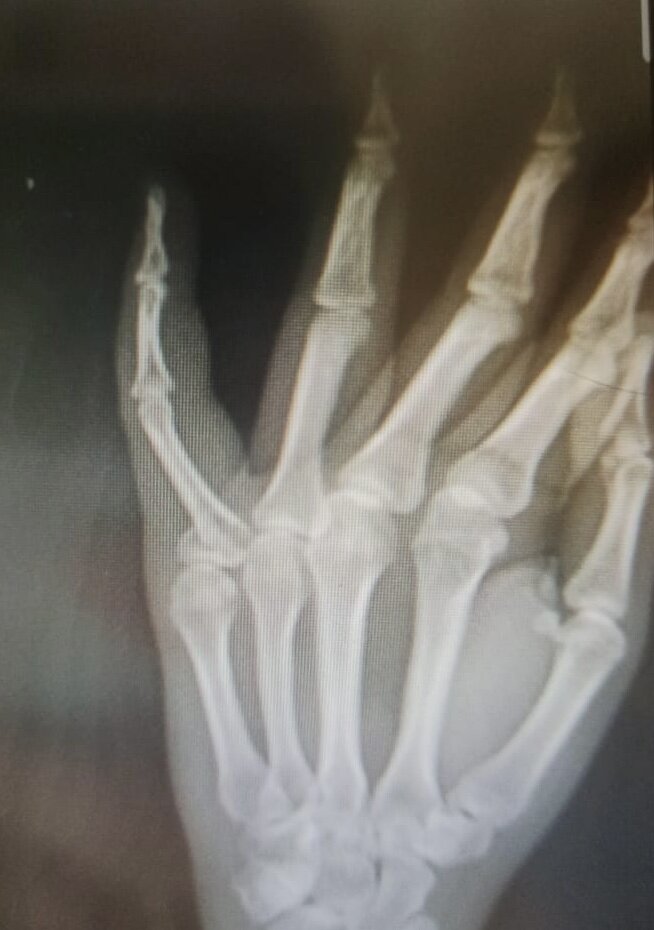

Улицы крупных городов сейчас буквально заполонил относительно новый для нас вид транспорта - электросамокаты. Причём, довольно травматичный, как оказалось. В интернете полно кадров со страшными падениями с такого безобидного (с виду) металического зверя и травмы (как сказали мне сегодня хирург и врачи скорой) бывают очень серьёзными (так что я ещё легко отделалась… А произошло все из-за моего состояния. Дело в том, что за несколько минут до падения я каталась на картинге и после таких ярких эмоций я, естественно, нормально не соображала (что и почувствовала сразу) На скорости у меня начала слетать кепка и я оторвала одну руку от руля, (что человек в нормальном состоянии на скорости около 25 км в час точно не сделал бы) естественно, у самоката сильно сместился центр тяжести и я упала, (ну а результат вы уже видели на снимке выше) Как сказали врачи, каждый день кого-то привозят с травмами из-за падений с самоката, и мне ещё очень повезло, потому что бывает куда посерьезней… На этом, по

… переломом со смещением осколка)

На скорости у меня начала слетать кепка и я оторвала одну руку от руля, (что человек в нормальном состоянии на скорости около 25 км в час точно не сделал бы) естественно, у самоката сильно сместился центр тяжести и я упала, (ну а результат вы уже видели на снимке выше)

Вот он )))